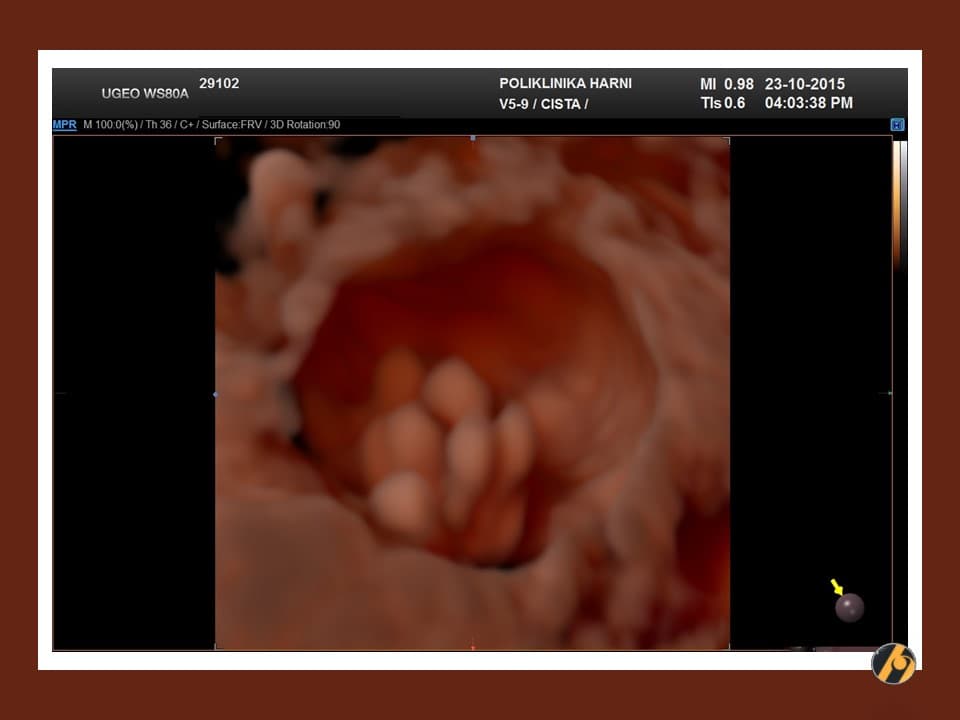

Papila

IOTA definicija papilarne projekcije je protruzija solidnog tkiva unutar cistične tvorbe u visini najmanje od 3 mm. Protruzija solidnog tkiva manje od 3 mm se ne smatra papilarnom projekcijom.

- Unilokularna solidna cista: unilokularna cista s jednom šupljinom i solidnom komponentnom. Solidna komponentna može biti papilarna projekcija ili bilo koji drugi tip solidnog tkiva.

- Multilokularni solidni tumor: sadrži i septa i solidne dijelove. Solidna komponentna može biti papilarna projekcija ili bilo koji drugi tip solidnog tkiva.